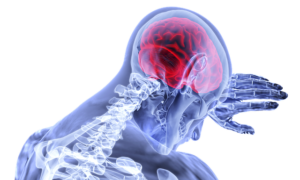

The brain, which is deeply connected to our spinal cord and nervous system, is just as susceptible.

A traumatic injury to the head can result in brain injury, which is a large cause of disability in the United States.

If you are one of the over million people who suffer from a traumatic brain injury, a brain injury attorney who understand the complexities of insurance law can help you receive the claim you deserve.

Thousands of people who suffer from a traumatic brain injury end up in a life threatening condition. Those who do not die from the injury may be hospitalized for an extremely long period of time.